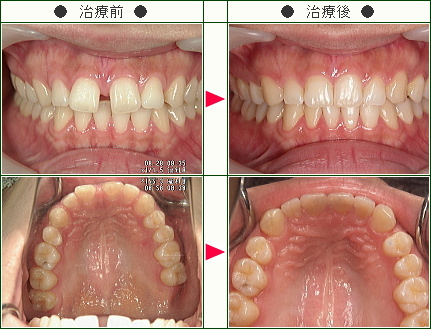

前歯のすきっ歯矯正の治療症例解説(20歳から39歳まで)--部分矯正--その2

☆前歯のすきっ歯矯正症例[T.N様 35歳 男性]